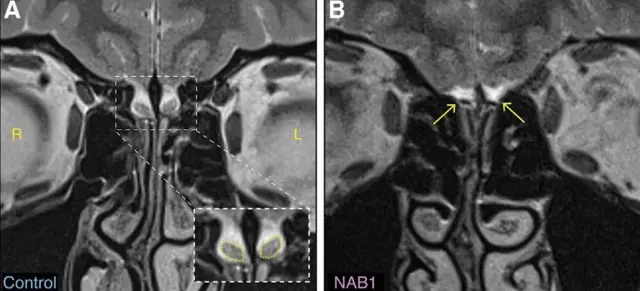

Istraživanje koje je objavljeno u časopisu Neuron pokazuje da neki ljudi imaju uobičajeno čulo mirisa, uprkos tome što im nedostaje deo mozga za koji se smatra da je presudan za miris - olfaktorne bulbuse.

Nedostatak tih bulbusa treba da izazove anosmiju (nesposobnost osobe da oseća mirise).

Ipak, do velikog otkrića došlo je kada su istraživači sa Vajcmanovog instituta za nauku u Izraelu otkrili da postoje ljudi koji imaju uobičajen miris iako nemaju te sijalice.

Autor fotografije, Weizmann Institute

Jedna od mogućnosti je da žene imaju olfaktorne bulbuse, ali da su one toliko male da ne mogu da se vide na nekim skenerima.